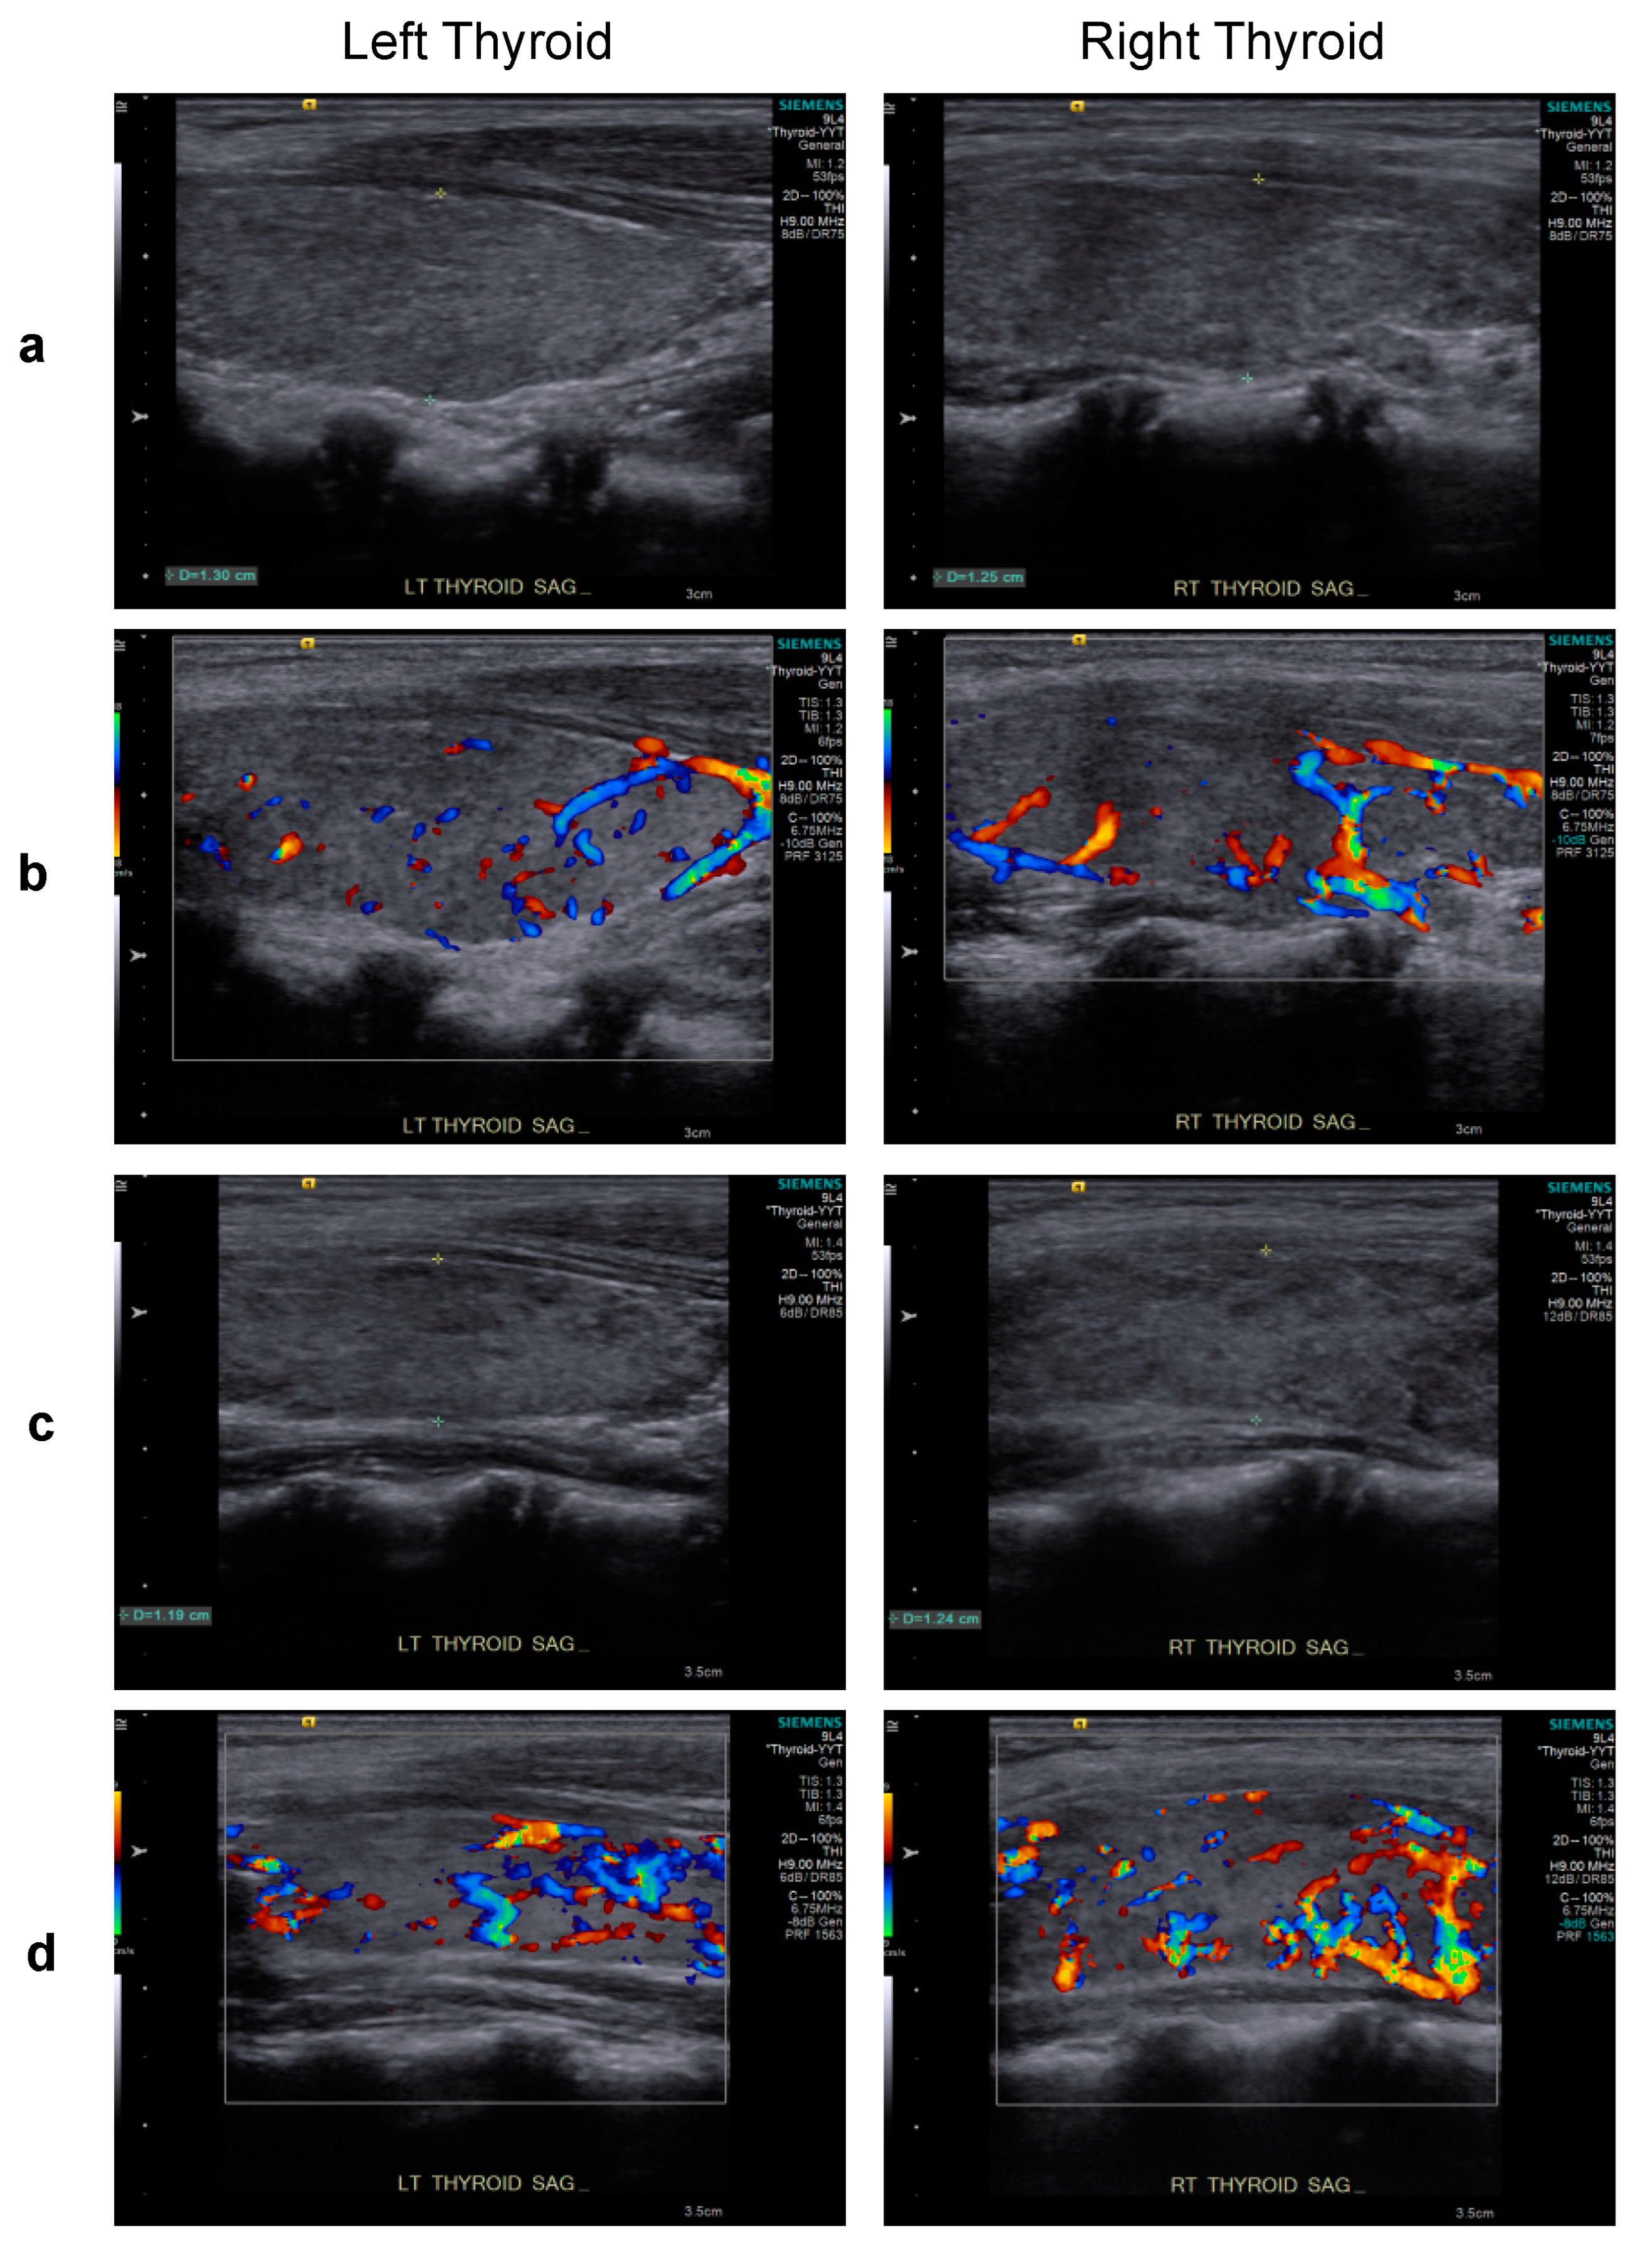

2. Case Report